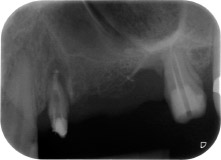

Fig. 1: En una paciente de 58 años, la radiografía previa a la intervención mostraba una lesión periodontal apical en la pieza dental 24, así como una pérdida horizontal de hueso alveolar en el segundo cuadrante.

Mujer de 58 años de edad, que además es una apreciada colega y amiga, y se quejaba de dolor y de un aumento en la movilidad del pilar del puente de la pieza dental 24. También había inflamación periodontal, con bolsas de una profundidad de 7 mm en sentido mesiobucal y más de 12 mm en sentido distal, así como furcación de tercer grado. Asimismo, la radiografía reveló una lesión periodontal extensa alrededor de la región apical de la pieza dental 24 (figura 1) tratada previamente con endodoncia (alio loco).